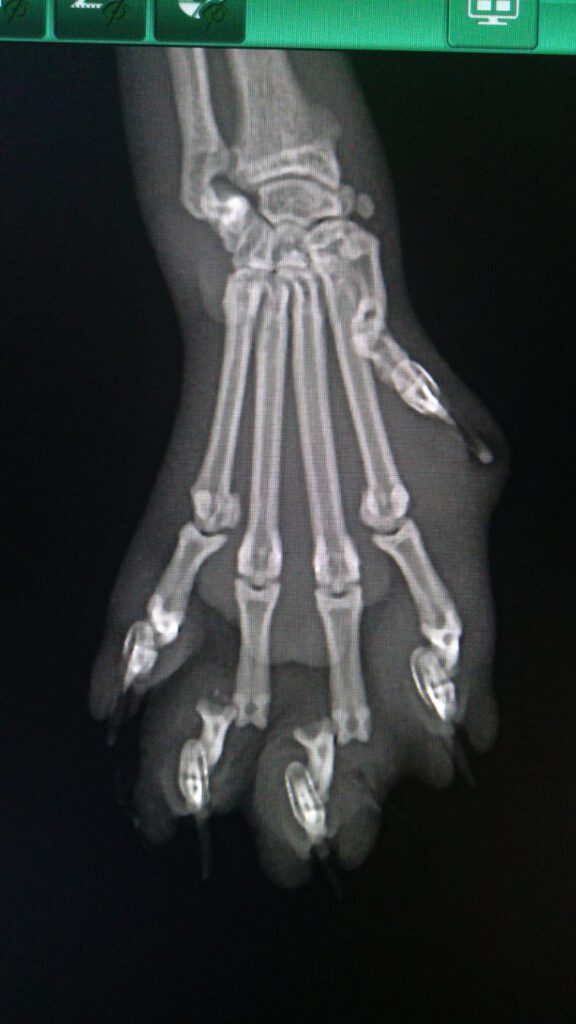

In der anschließenden Behandlung stellte sich heraus, dass die Katze neben erheblichen Verletzungen an der Pfote auch metallische Gegenstände, vermutlich die Befestigung des Köders, in Körper hatte. Die Veröffentlichung der Röntgenbilder wurden vom Tierarzt genehmigt.